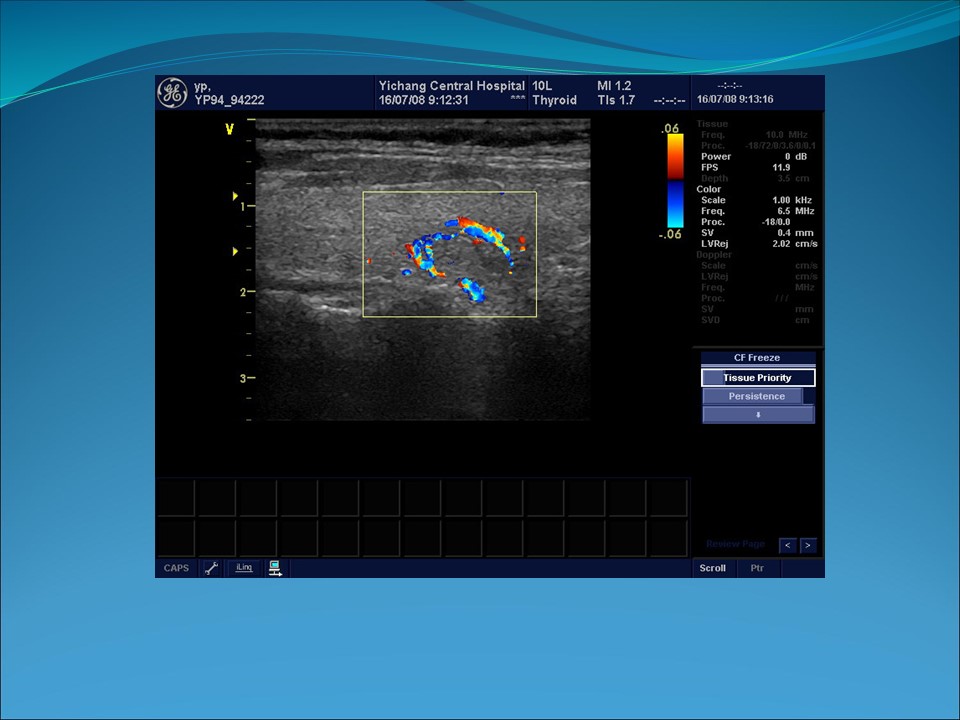

声像图特点:

4、CDFI:无特征性,偶可见血流信号增多、散在分布、无规律性。